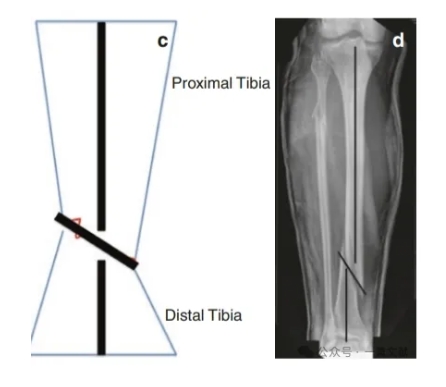

小螺钉解决大问题:阻挡螺钉的应用技巧!